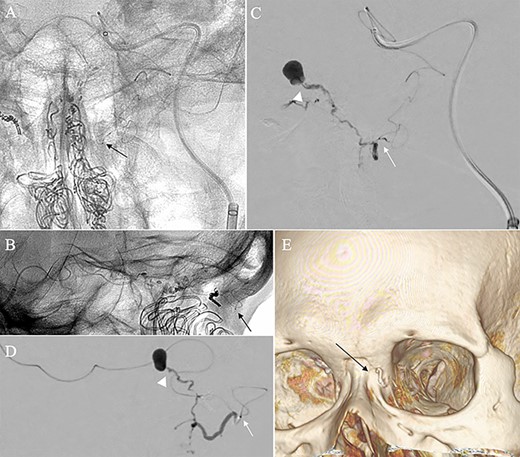

A patient in their 70s with extracranial lymphoma was incidentally found to have ACF–dAVF via head computed tomography and magnetic resonance angiography. Digital subtraction angiography (DSA) confirmed ACF–dAVF with multiple feeding branches, arising from bilateral OphAs, distal IMAs and the left middle meningeal artery (MMA), with cortical venous reflex (Borden type III, Cognard type IV) (Fig. 1). At the patient’s request, we chose endovascular, rather than surgical, treatment. We injected a 20% N-butyl-2-cyanoacrylate (NBCA)–lipiodol mixture into the fistula through bilateral ethmoidal arteries and the left MMA after we placed coils at the terminal branch of the right OphA. However, we could not achieve full penetration into the fistulous connections because of pressure secondary to high flow from the IMA branches, which resulted in incomplete obliteration (Fig. 1). Four months later, we repeated TAE by temporarily reducing nasal blood flow by inserting gauze infiltrated with xylocaine and epinephrine into the nasal cavities. After introducing the guiding catheter, an endonasal surgeon inserted X-ray-detectable surgical gauze infiltrated with 1% xylocaine and epinephrine (1:10 000) into bilateral nasal cavities using a nasal speculum, while paying full attention to avoid damage to the nasal mucosa. Then, we confirmed that the gauzes were placed in appropriate locations in the upper nasal cavity under fluoroscopic guidance. Immediately after insertion, we were able to confirm decreased blood flow from the IMA using DSA (Fig. 2). After this procedure, we navigated a DeFrictor Nano Catheter (Medico’s Hirata, Osaka, Japan) into the terminal branch of the OphA, which was connected to the dorsal nasal artery. Even though there was still a distance from the tip of the microcatheter to the shunt pouch, the NBCA reached the shunt point and penetrated the venous portion (Fig. 3). Follow-up DSA demonstrated complete obliteration of the ACF–dAVF, and blood flow in the nasal mucosa from the IMA branches recovered normally (Fig. 4).

Right (A) and left (B and C) internal carotid artery angiography before initial treatment showing ACF–dAVF with feeding arteries arising from branches of the OphAs; ethmoid artery (arrow) and dorsal nasal artery (arrowhead) (D and E). Bilateral external carotid artery angiography before initial treatment, anteroposterior view, showing the ACF–dAVF fed by bilateral distal internal maxillary arteries and the left middle meningeal artery.

Angiographic images, anteroposterior (A) and lateral (B) views, showing the microcatheter (arrow) navigated into the terminal branch of the left terminal branch of the ophthalmic artery, which connects to the dorsal nasal artery. Digital subtraction angiography, anteroposterior (C) and lateral (D) views, showing NBCA injected via the microcatheter (arrow) penetrating into the shunt point (arrowhead) without reflux of the NBCA. (E) Three-dimensional reconstruction of the skull showing the NBCA cast (arrow), which was embolized via the dorsal nasal artery.